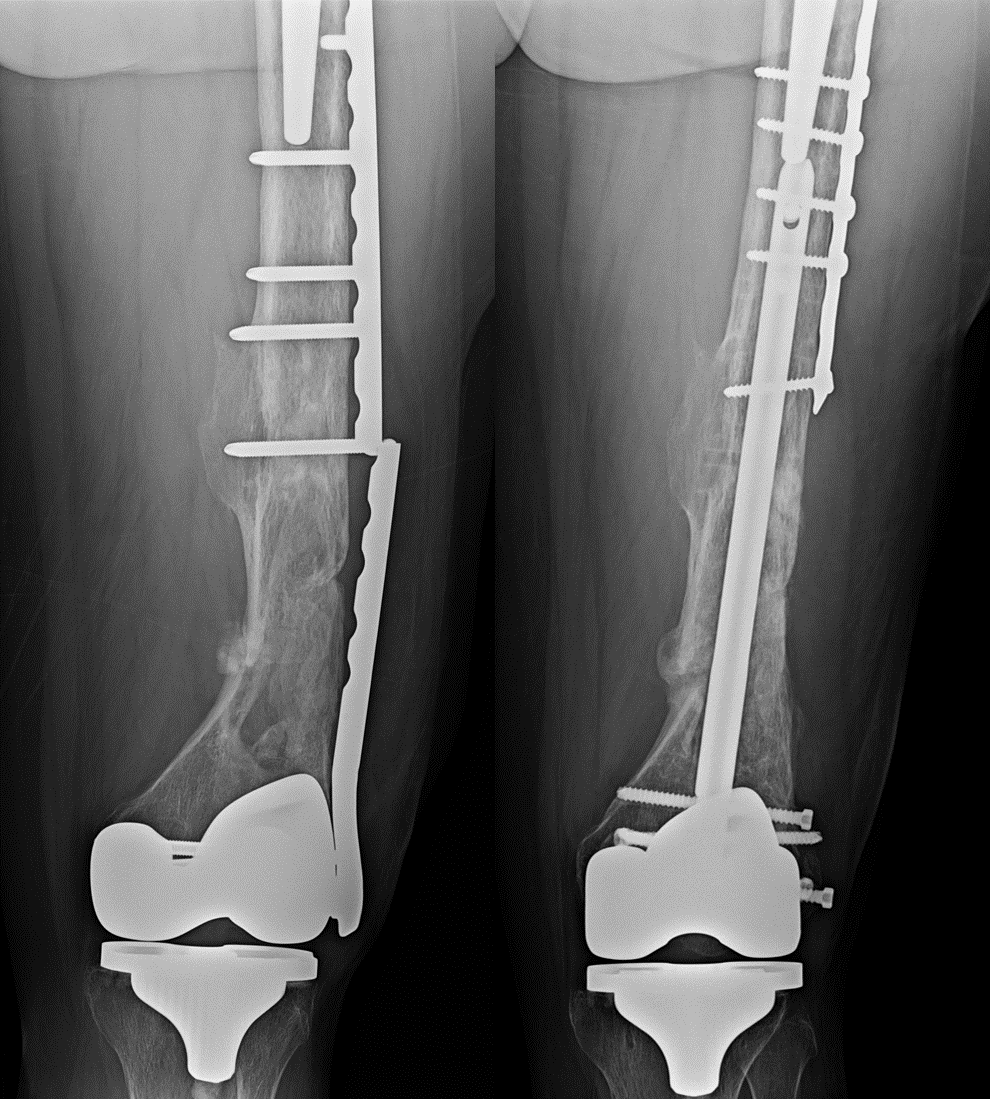

Pediatric lateral condyle fractures are the second most common fractures in the pediatric elbow and are characterized by a higher risk of nonunion, malunion, and avn than other pediatric elbow fractures. Trauma to the mandible often causes condylar fracture. Fractures without the reduction of the condylar height;

This report presents the experience acquired in the treatment of 466 condylar fractures. Treatment option for children with condylar fracture. Condylar fracture classification is defined according to spiessl & schroll. Fracture of the mandibular condyle, all treated closed, were included in the study. At first moth, 3rd month, 6th month, 1 year, then every year after first treatment, cbct is performed. The incidence of condylar fractures among the various mandibular fractures ranges from 17.5% to 52%.1,2 but condylar open versus closed treatment of. For that reason, among others, most surgeons choose closed treatment for these joint fractures. Pediatric lateral condyle fractures are the second most common fractures in the pediatric elbow and are characterized by a higher risk of nonunion, malunion, and avn than other pediatric elbow fractures. Condylar fractures can be extracapsular purpose: In literature fractures of the mandible that involve the condyle ranges from 20% to up to the present, numerous techniques have been used for the surgical treatment of condylar fractures. Trauma to the mandible often causes condylar fracture. Mandibular condylar fracture is one of the commonest maxillofacial fractures treated by open treatment of fracture of head of mandibular condyle is controversial; Schug t., rodemer h., neupert w et al. A obvious scar at the temporal region, affecting the placement of the original incision. Treatment of complex mandibular fracture using titanium ziccardi v.b. Of mandibular function and pain after closed treatment of condylar fractures is good. This has led some clinicians to seek alternative methods of treatment, including the use of rigid internal fixation.